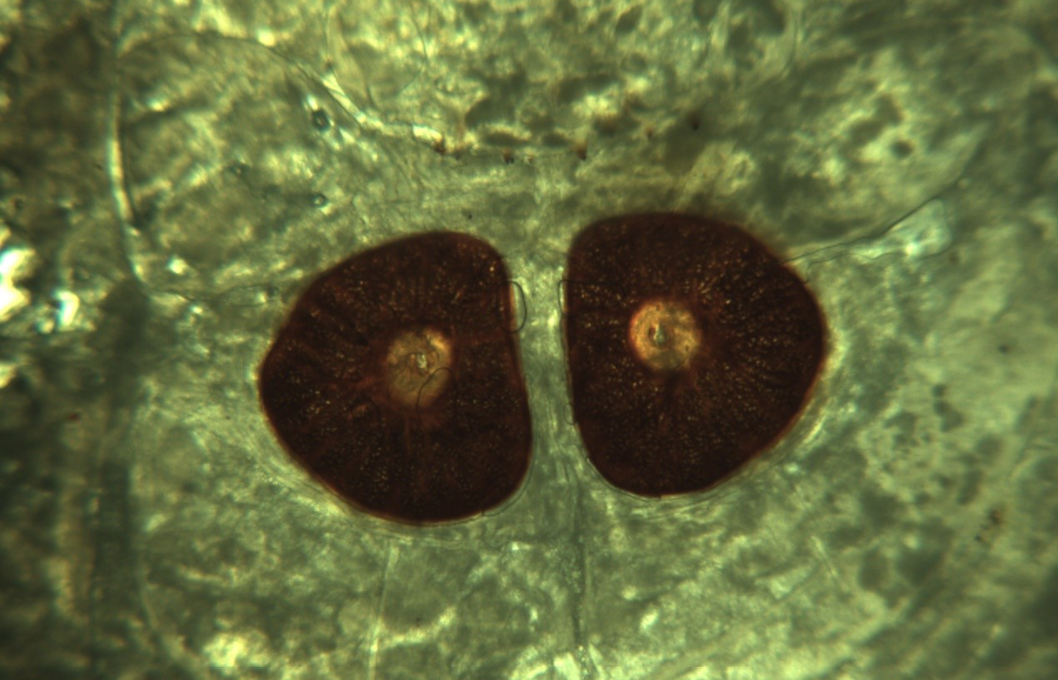

Figure 4

D–shaped closed, dark black coloured, stigmal plates with radially arranged respiratory holes (under 4x microscopy)